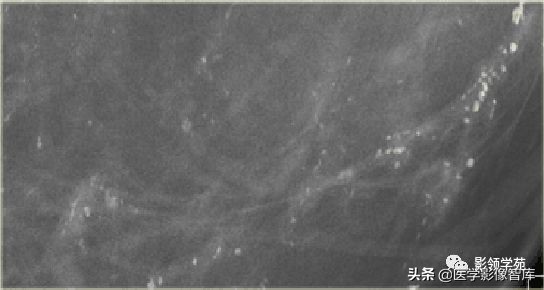

细小线样或细小分枝状

细小的线样或弯曲不规则钙化,通常<0.5mm,暗示管腔充填,如“铸形” 。通常为BI-RADS5

阶段性分布,其中有些呈线样分布 BI-RADS5

BI-RADS 5 活检证实高级DCIS

线状分布:沿导管方向线状分布:手术病理:浸润性导管癌。